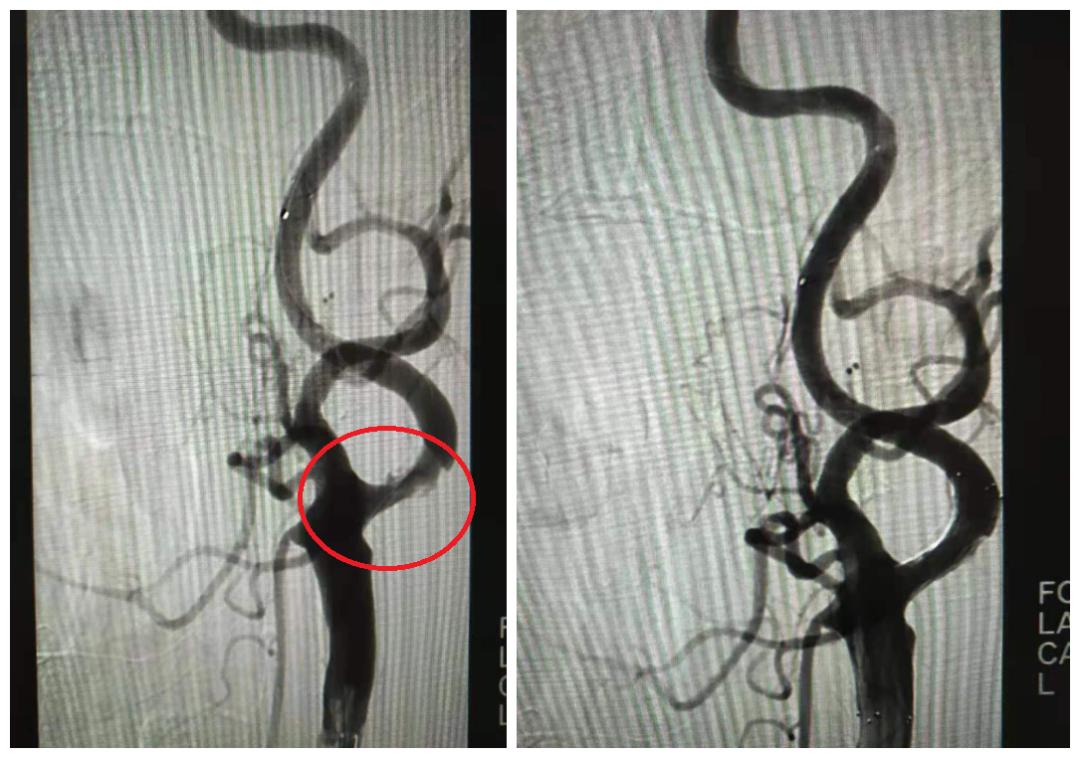

住院治疗三个星期后,谈大爷的身体状况符合 DSA介入治疗的指征 。手术过程很顺利,术后恢复情况良好,目前谈大爷已康复出院。

右颈C1支架置入术前(左)术后(右)

左颈C1支架置入术前(左)术后(右)